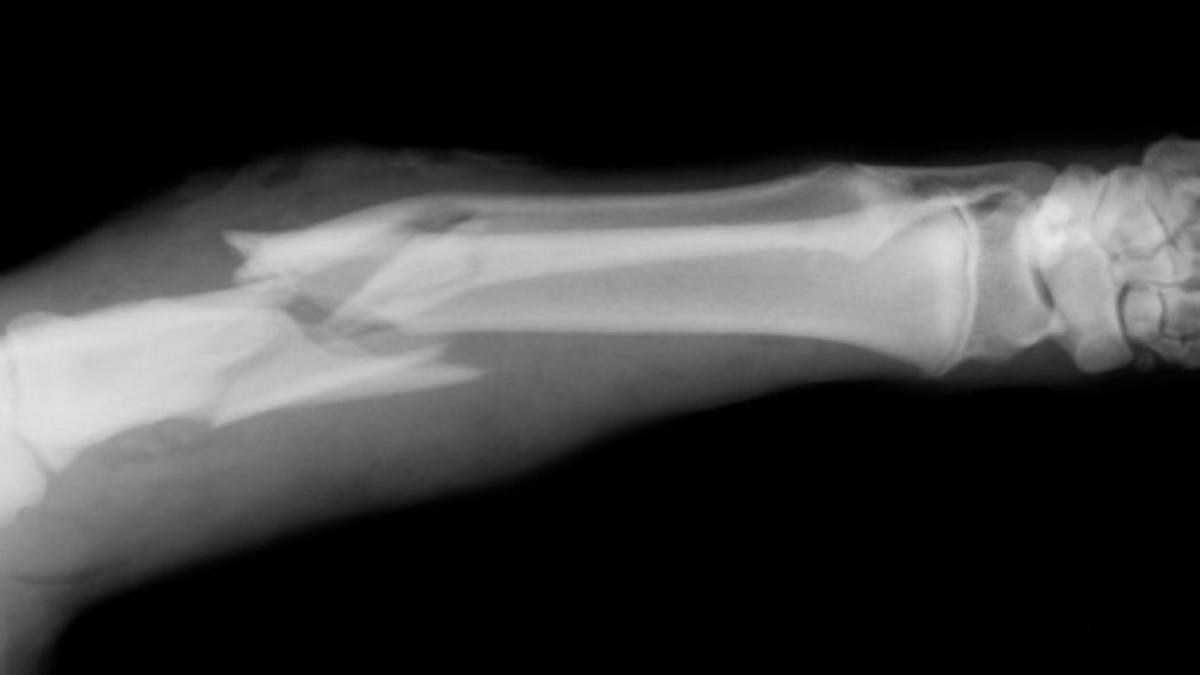

Fazlasıyla yanlış ve tehlikeli bir düşünce daha. Kırığın çapı, herhangi bir tendon yırtığı olup olmadığı bilinmeden kaderine terk etmek oldukça yanlıştır. Nitekim parmak kırıklarının iyileşme süreci 4-6 hafta periyodundadır ve bu süreçte kötü açılardan oluşan kırıklar geri dönülemez yaralanmalara sebep olabilir.